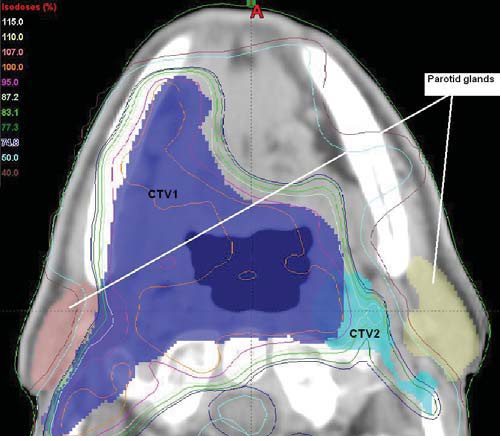

Irradiation was given on a linear accelerator ( 6 MV Siemens Oncor Expression ) and all patients were immobilized using custom made masks. IMRT was delivered using the Linatech planning system; 95% of the Planning Target Volume (PTV) had to receive 95% of the prescribed dose. The aim was to reduce the mean dose to 26 Gy or less for at least one parotid gland (Fig. 1). Sparing of the submandibular glands or oral cavity was not attempted.

parotid gland Figure 1: IMRT plan demonstrating left parotid gland

sparing.

CTV1 - primary tumour and high risk nodes.

CTV2 � nodes at risk of micrometastases.

(CTV : Clinical Target Volume)